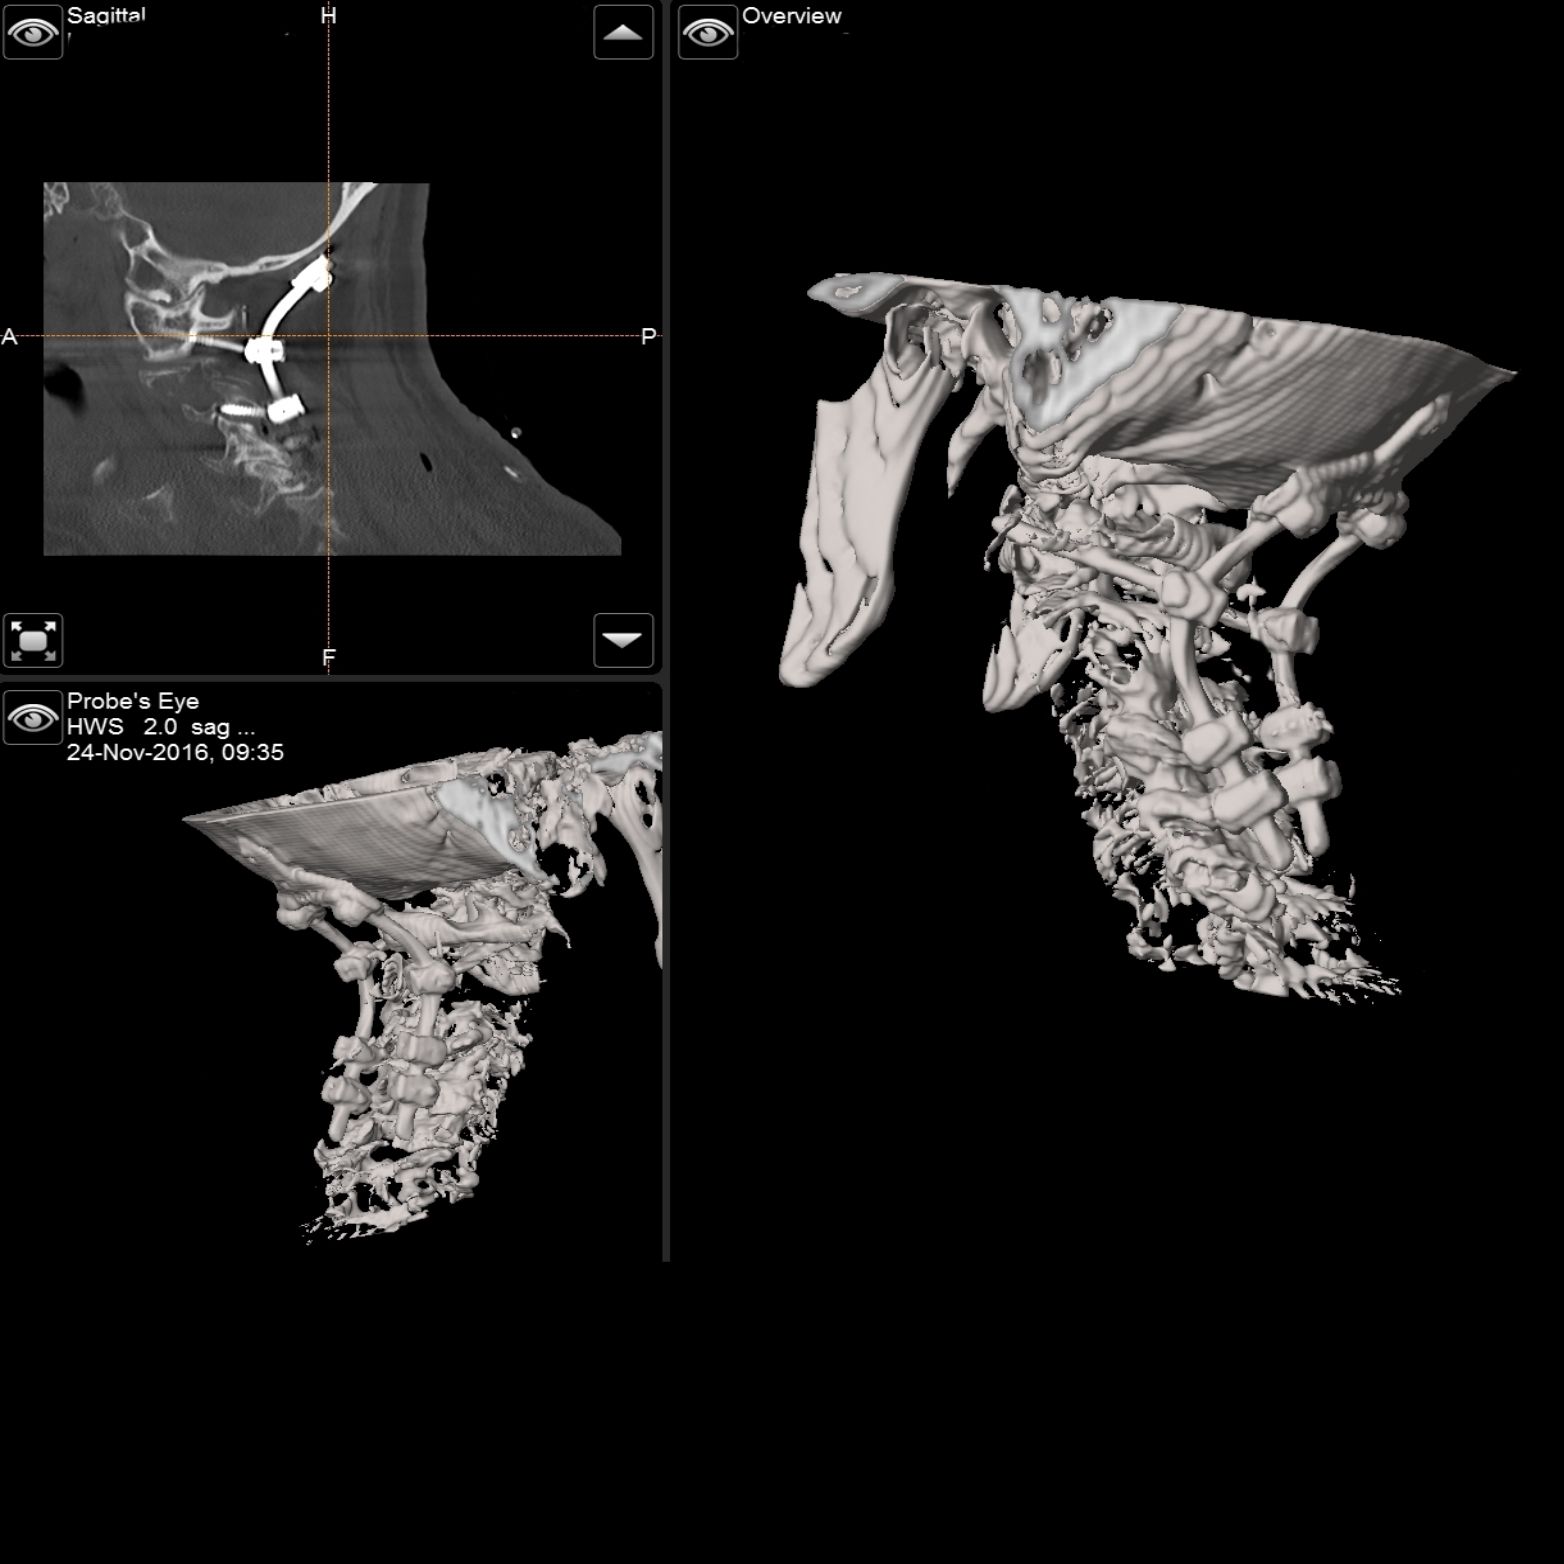

Intraoperativer Röntgen

C-Bogen mit

3D Rekonstruktion

Die Universitätsklinik Tübingen verfügt über hochmoderne mobile Bildgebungssysteme, darunter der robotisch geführte digitale Volumentomograph Loop-X der Firma Brainlab sowie ein mobiler 3D-C-Bogen der Firma Ziehm. Diese fortschrittlichen Systeme ermöglichen intraoperativ eine präzise 3D-Rekonstruktion des Kopfes oder der Wirbelsäule. Für die Kopf- und Wirbelsäulenchirurgie kann mithilfe dieser Technologien ein Navigationsdatensatz erstellt werden, der eine hochpräzise Navigation gewährleistet. So können beispielsweise Schrauben in der Wirbelsäule exakt platziert und kontrolliert oder Trajektorien für Zugangswege und Probenentnahmen im Kopf definiert werden.